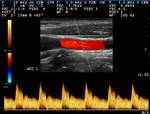

Beispiele für Duplexbefunde:

Plaquebildung in der Arteria carotis interna

Normalbefund der Arteria carotis interna

Normalbefund der Arteria carotis communis